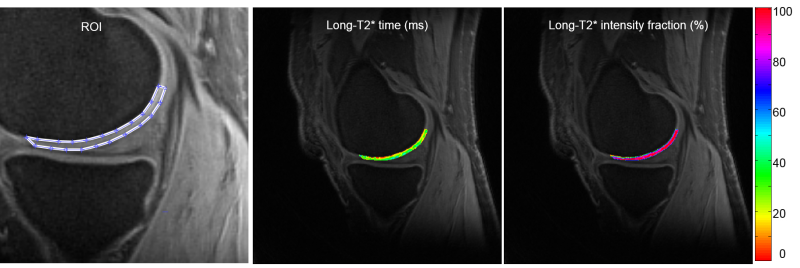

pM2 is a MATLAB-based standalone deployment which can run in a personal computer without MATLAB installed in it. pM2 performs curve fitting to a model of two exponential decays and one constant term: s(t) = A21*exp(-t/T21) + A22*exp(-t/T22) + C + n(t), on a pixel-by-pixel basis in a region of interest (ROI). pM2 uses an iterative NNLS (non-negative least squares) algorithm to search the best fitting at each pixel. It produces seven maps: a21, T21, a22, T22, T2mono, and two R-square (R2). pM2 also calculates the mean and standard deviation (SD) of these fitted parameters

in a user-defined ROI. To define ROI, a separate software will be provided to you for free. An example of pM2 mapping is shown in Figure 2 below. The software package includes a user manual which details how to install and run pM2 on your computer.

Uploading your DICOM images is required. Curve fitting to a two-component model: s(t) = A21*exp(-t/T21) + A22*exp(-t/T22) + C + n(t), on a pixel-by-pixel basis in a region of interest (ROI). Use an iterative NNLS (non-negative least squares) algorithm for the fitting at each pixel. Produce seven maps: a21, T21, a22, T22, T2mono, and two R-square (R2). Calculate their means and standard deviations (SD) in a user-defined ROI. To define ROI, a separate software will be provided to you for free. An example of pM2 mapping is shown in Figure 2 below.

a

b

Figure 2. pM2 bi-component T2* mapping. (a) ROI, long-component T2* time and intensity fraction, (b) short-component T2* time, intensity fraction, and single-component-fitted T2* time.